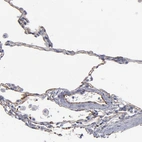

Immunohistochemical staining of human Ovarian cancer shows strong positivity in tumor cells.